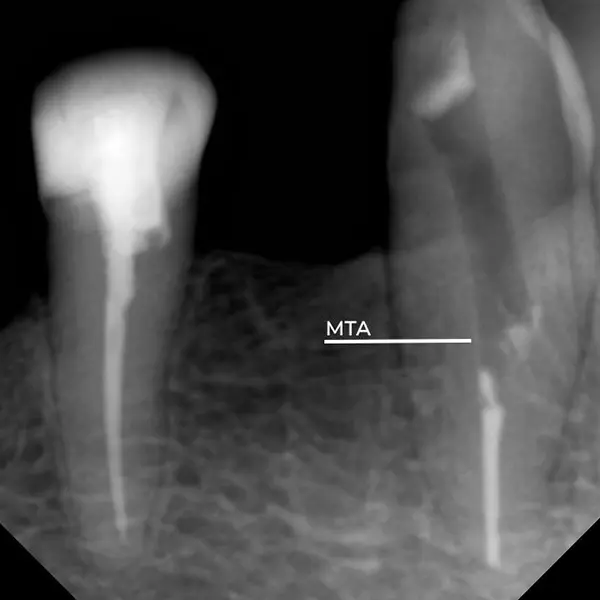

- Стоматологический порошок для ретроградного пломбирования: специальный порошок использовался для перекрытия сформированной “ступени” (изгиба или резкого изменения конусности), обеспечивая герметичность.